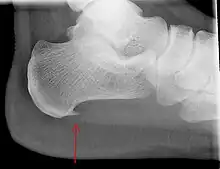

An incidental finding associated with this condition is a heel spur, a small bony calcification on the calcaneus (heel bone), which can be found in up to 50% of those with plantar fasciitis.[6] In such cases, it is the underlying plantar fasciitis that produces the heel pain, and not the spur itself.[13] The condition is responsible for the creation of the spur though the clinical significance of heel spurs in plantar fasciitis remains unclear.[12]

Imaging

Medical imaging is not routinely needed. It is expensive and does not typically change how plantar fasciitis is managed.[15] When the diagnosis is not clinically apparent, lateral view X-rays of the ankle are the recommended imaging modality to assess for other causes of heel pain, such as stress fractures or bone spur development.[7]

The plantar fascia has three fascicles-the central fascicle being the thickest at 4 mm, the lateral fascicle at 2 mm, and the medial less than a millimeter thick.[19] In theory, plantar fasciitis becomes more likely as the plantar fascia's thickness at the calcaneal insertion increases. A thickness of more than 4.5 mm ultrasound and 4 mm on MRI are useful for diagnosis.[20] Other imaging findings, such as thickening of the plantar aponeurosis, are nonspecific and have limited usefulness in diagnosing plantar fasciitis.[13]